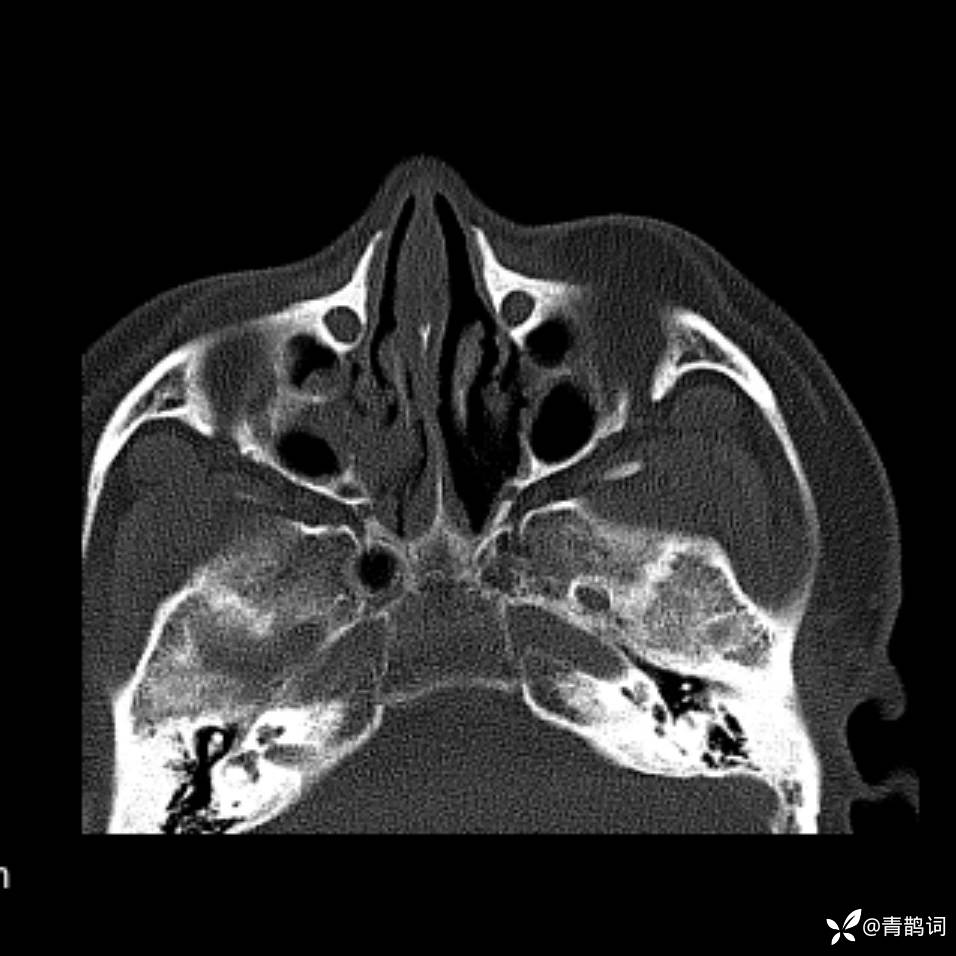

患者年龄:30岁。

患者性别:男。

简要病史:左颜面部肿胀2年,反复咳嗽咳痰,逐渐加重。

结合病史及影像学表现,期待评论区各位老师各抒己见~

木村病 (14)